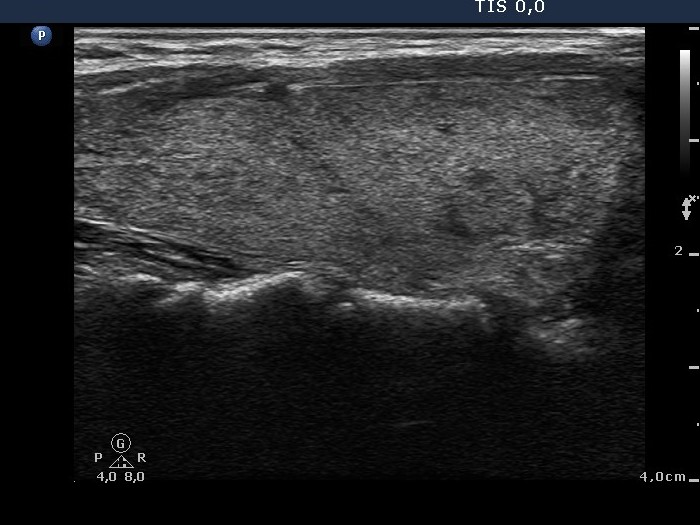

Graves' disease - Case 15.

Follow-up investigation 36 months after first visit (ultrasonographic picture 2)

Patient on daily 10 mg methimazole therapy in euthyroid state

Right lobe, longitudinal scan.